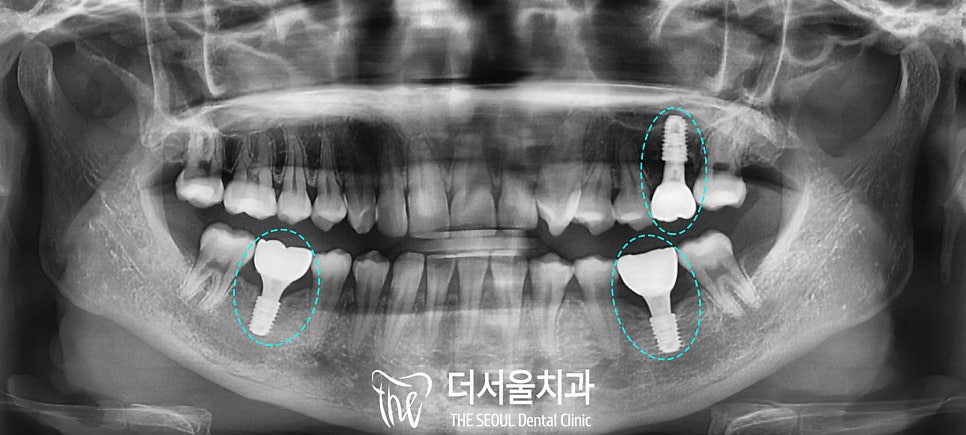

다행히 골소실이

그렇게 심하지 않아

잔존 치근은 깨끗하게 뽑았으며

원했던 위치에

잘 심어진 것을 확인할 수 있습니다.

4. 크라운 수복

성남 치과 에서는

환자의 골질, 치조골의 양,

염증의 크기, 잇몸 상태 같은

여러 조건에 따라

각각 충분한 회복 기간을 갖습니다.

또한 위치에 따라

치조골과 더 빠르게 잘 결합되는 부위를

우선으로 안정적인 고정력이 나왔다면

지르코니아 보철 제작을 시작하여

최종 크라운까지

모두 올린 구강 내 모습인데요,

상악은 곳곳의 거뭇거뭇 한

충치도 모두 제거하고 때워드렸습니다.

그리고 우식이 심했던

왼쪽 위 어금니와

양측 아래 어금니는

디지털 임플란트에 딱 맞는

크라운을 연결해 드렸습니다.